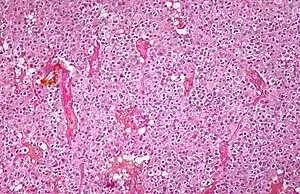

Micrograph of an oligodendroglioma showing the characteristic branching, small, chicken wire-like blood vessels and fried egg-like cells, with clear cytoplasm and well-defined cell borders. H&E stain. | |

Oligodendrogliomas cannot currently be differentiated from other brain lesions solely by their clinical or radiographic appearance. As such, a brain biopsy is the only method of definitive diagnosis. Oligodendrogliomas recapitulate the appearance of the normal resident oligodendroglia of the brain. (Their name derives from the Greek roots 'oligo' meaning "few" and 'dendro' meaning "trees".) They are generally composed of cells with small to slightly enlarged round nuclei with dark, compact nuclei and a small amount of eosinophilic cytoplasm. They are often referred to as "fried egg" cells due to their histologic appearance. They appear as a monotonous population of mildly enlarged round cells infiltrating normal brain parenchyma and producing vague nodules. Although the tumor may appear to be vaguely circumscribed, it is by definition a diffusely infiltrating tumor.[6]

Classically they tend to have a vasculature of finely branching capillaries that may take on a "chicken wire" appearance. When invading grey matter structures such as cortex, the neoplastic oligodendrocytes tend to cluster around neurons exhibiting a phenomenon referred to as "perineuronal satellitosis". Oligodendrogliomas may invade preferentially around vessels or under the pial surface of the brain.[6]